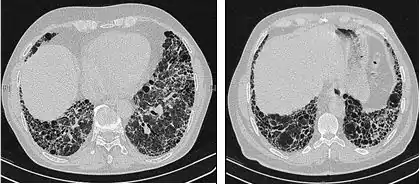

The radiological evaluation through HRCT is an essential point in the diagnostic pathway in IPF. HRCT is performed using a conventional computed axial tomographic scanner without injection of contrast agents. Evaluation slices are very thin, 1–2 mm.

Typical HRCT of the chest of IPF demonstrates fibrotic changes in both lungs, with a predilection for the bases and the periphery. According to the joint ATS/ERS/JRS/ALAT 2011 guidelines, HRCT is an essential component of the diagnostic pathway in IPF which can identify UIP by the presence of:[3]

- Reticular opacities, often associated with traction bronchiectasis

- Honeycombing manifested as cluster cystic airspaces, typically of comparable diameters (3–10 mm) but occasionally large. Usually sub-pleural and characterized by well-defined walls and disposed in at least two lines. Generally one line of cysts is not sufficient to define honeycombing

- Ground-glass opacities are common but less extensive than the reticulation

- Distribution characteristically basal and peripheral though often patchy.